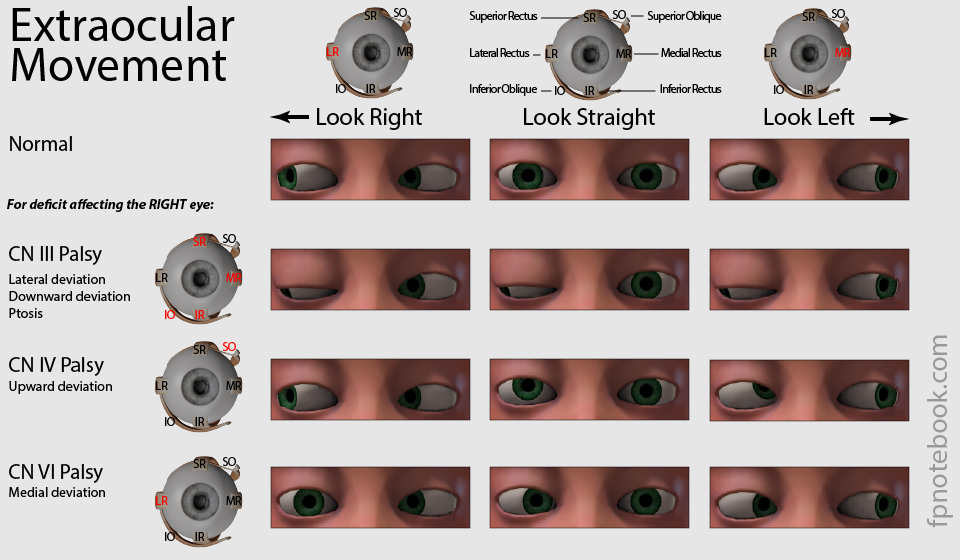

Ocular Movements & Visual Reflexes - Medatrio

medatrio.com

medatrio.com

movements ocular strabismus reflexes visual eye extraocular medial squint weakness medially right laterally muscles paralysis producing

Cranial Nerve 6

www.fpnotebook.com

www.fpnotebook.com